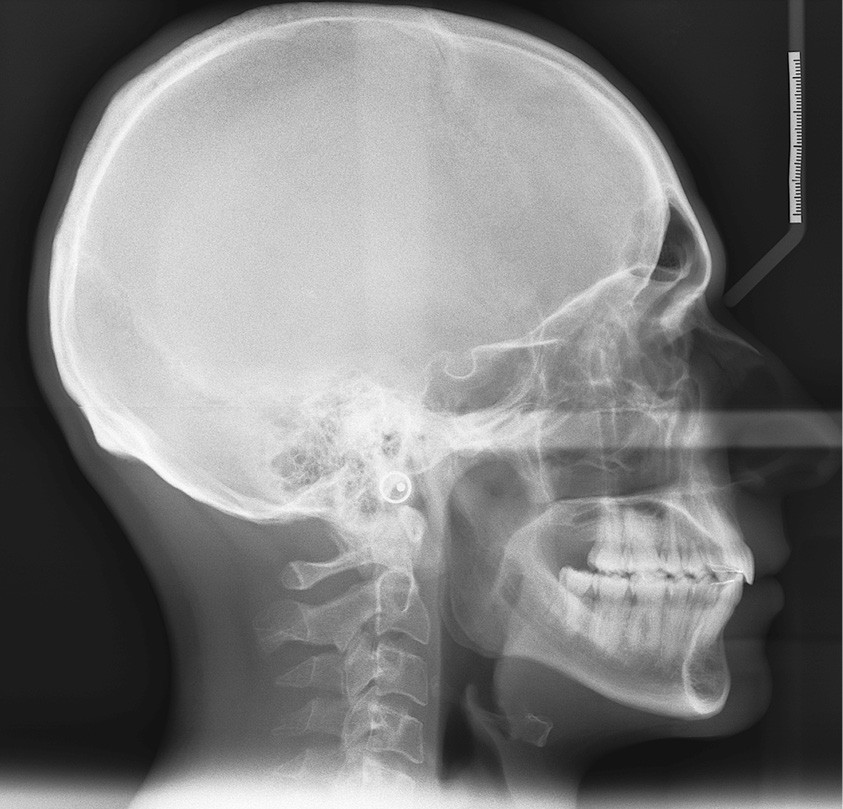

Le patient consulte initialement pour des défauts d’alignement. L’examen clinique confirme l’existence d’un encombrement antérieur bimaxillaire, mais révèle aussi la présence d’une Classe II dentaire sévère, d’une exoclusion de la 27 et de troubles parodontaux (peu ou absence de papilles inter-dentaires). Sur le plan squelettique, le patient est relativement équilibré avec un profil harmonieux.

La sévère Classe II dentaire pourrait suggérer d’avoir recours à une chirurgie orthognathique par avancée mandibulaire, mais le menton est bien placé dans le profil. Sa correction doit donc être orthodontique.